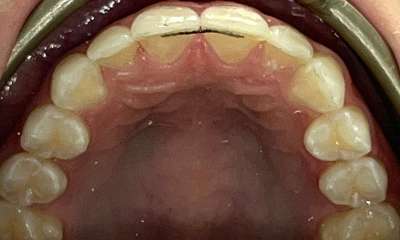

This patient presented with concerns about the damage his teeth had sustained from his bite and previous habits. His lower teeth had caused erosion and wear on the palatal surfaces and incisal edges of his upper front teeth. He was also concerned about the crowding of the lower front teeth. His primary goal was to create a more protected alignment and function of his teeth to support better oral health and longevity.

Due to a sensitive gag reflex, he first trialled nightly whitening trays for two weeks to assess whether he could tolerate aligner wear. This approach gave him the confidence ...